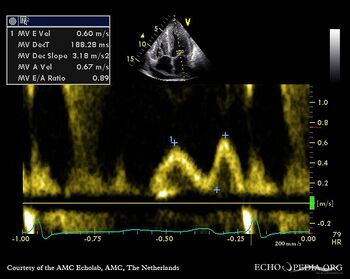

| Case description: This patient had amyloidosis with severe cardiac involvement

Mitral valve inflow E<A a sign of diastolic dysfunction